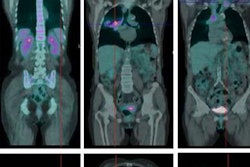

The analysis revealed a Kirsten rat sarcoma (KRAS) viral mutation in 96 patients (28%) and an epidermal growth factor receptor (EGFR) mutation in 44 patients (13%). The results indicate that EGFR mutations may drive different metabolic tumor phenotypes that are captured in PET images, while KRAS-mutated tumors do not.

FDG-PET shows patients with EGFR mutation, KRAS mutation, and EGFR-negative and KRAS-negative tumors. Stage I tumors (top) and stage III tumors (bottom) are shown, with arrows indicating the locations of the lung tumors. Image courtesy of Stephen S.F. Yip, PhD; Hugo Aerts, PhD; Dr. John Kim; and JNM.